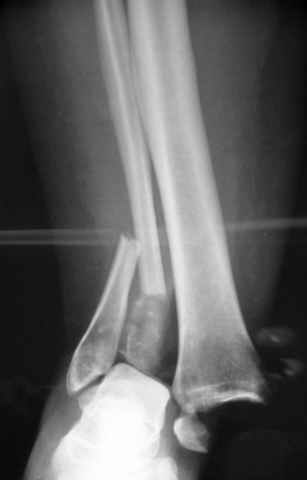

Pilon fracture:

-Появляется ориентир и остов, на чем можно строить восстановление, почему сперва малоберцовую, впервые обьяснили и описали (Pylon type and Ankle fractures) в середине 50х Rienau и Gay.

Восстановливая длину и ротацию малоберцовой кости, затем относительно легче произвести реставрацию остальных элементов перелома дистального эпиметафиза болшеберцовой кости.

конец малоберцевой кости, к нему прикрепляется латеральный суставной фрагмент дистального эпиметафиза большеберцовой кости (как на снимке)

и таранная кость, которые при репозиции малоберцовой кости репонируются автоматически.